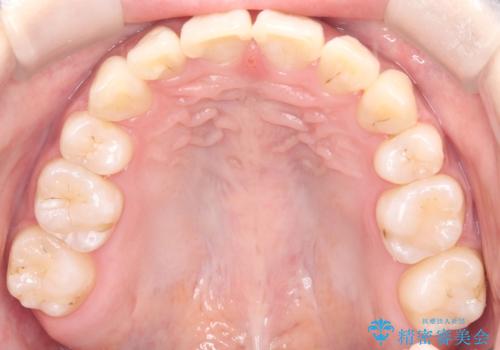

- 八重歯(叢生)と、上下の歯の中心線(正中)がずれていることを主訴にご来院されました。精密な検査の結果、歯列全体のスペースが大幅に不足しており、八重歯を正しい位置に配列し、正中のズレを改善するためには、上下左右の第一小臼歯を抜歯する必要があると診断。装置には、目立ちにくい審美ワイヤーを使用し、見た目を気にせず、機能性と審美性が完璧に整った咬み合わせを目指す治療計画を立案しました。

今回の矯正治療では、まず計画通り上下左右の小臼歯4本を抜歯し、八重歯や正中のズレを解消するための十分なスペースを確保しました。装置には、目立ちにくい白いブラケットとワイヤーを使用した審美ワイヤー矯正を採用。

八重歯: 突出していた八重歯を歯列内に誘導し、デコボコを解消しました。